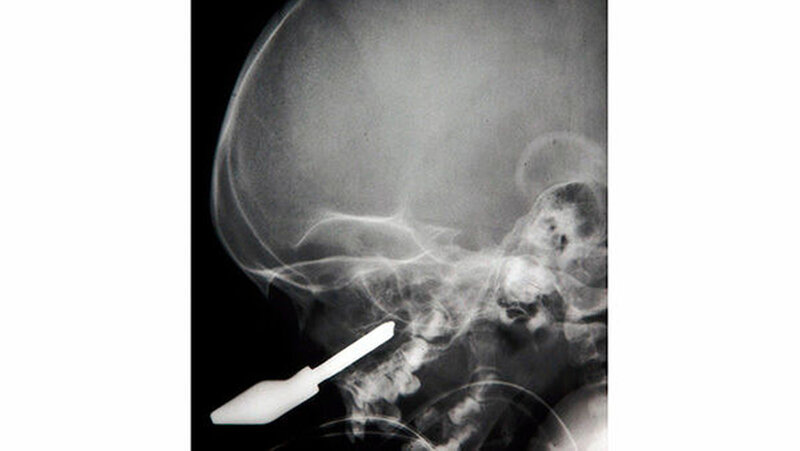

Vom Bohrer im Kopf bis zum Schlüssel in der Kieferhöhle: Die MKG-Chirurgen der Charité haben ausgewählte Patientenfälle mit Fremdkörpern im Gesicht zusammengestellt. In unserer Fotostrecke finden Sie die eindrucksvollen Aufnahmen.